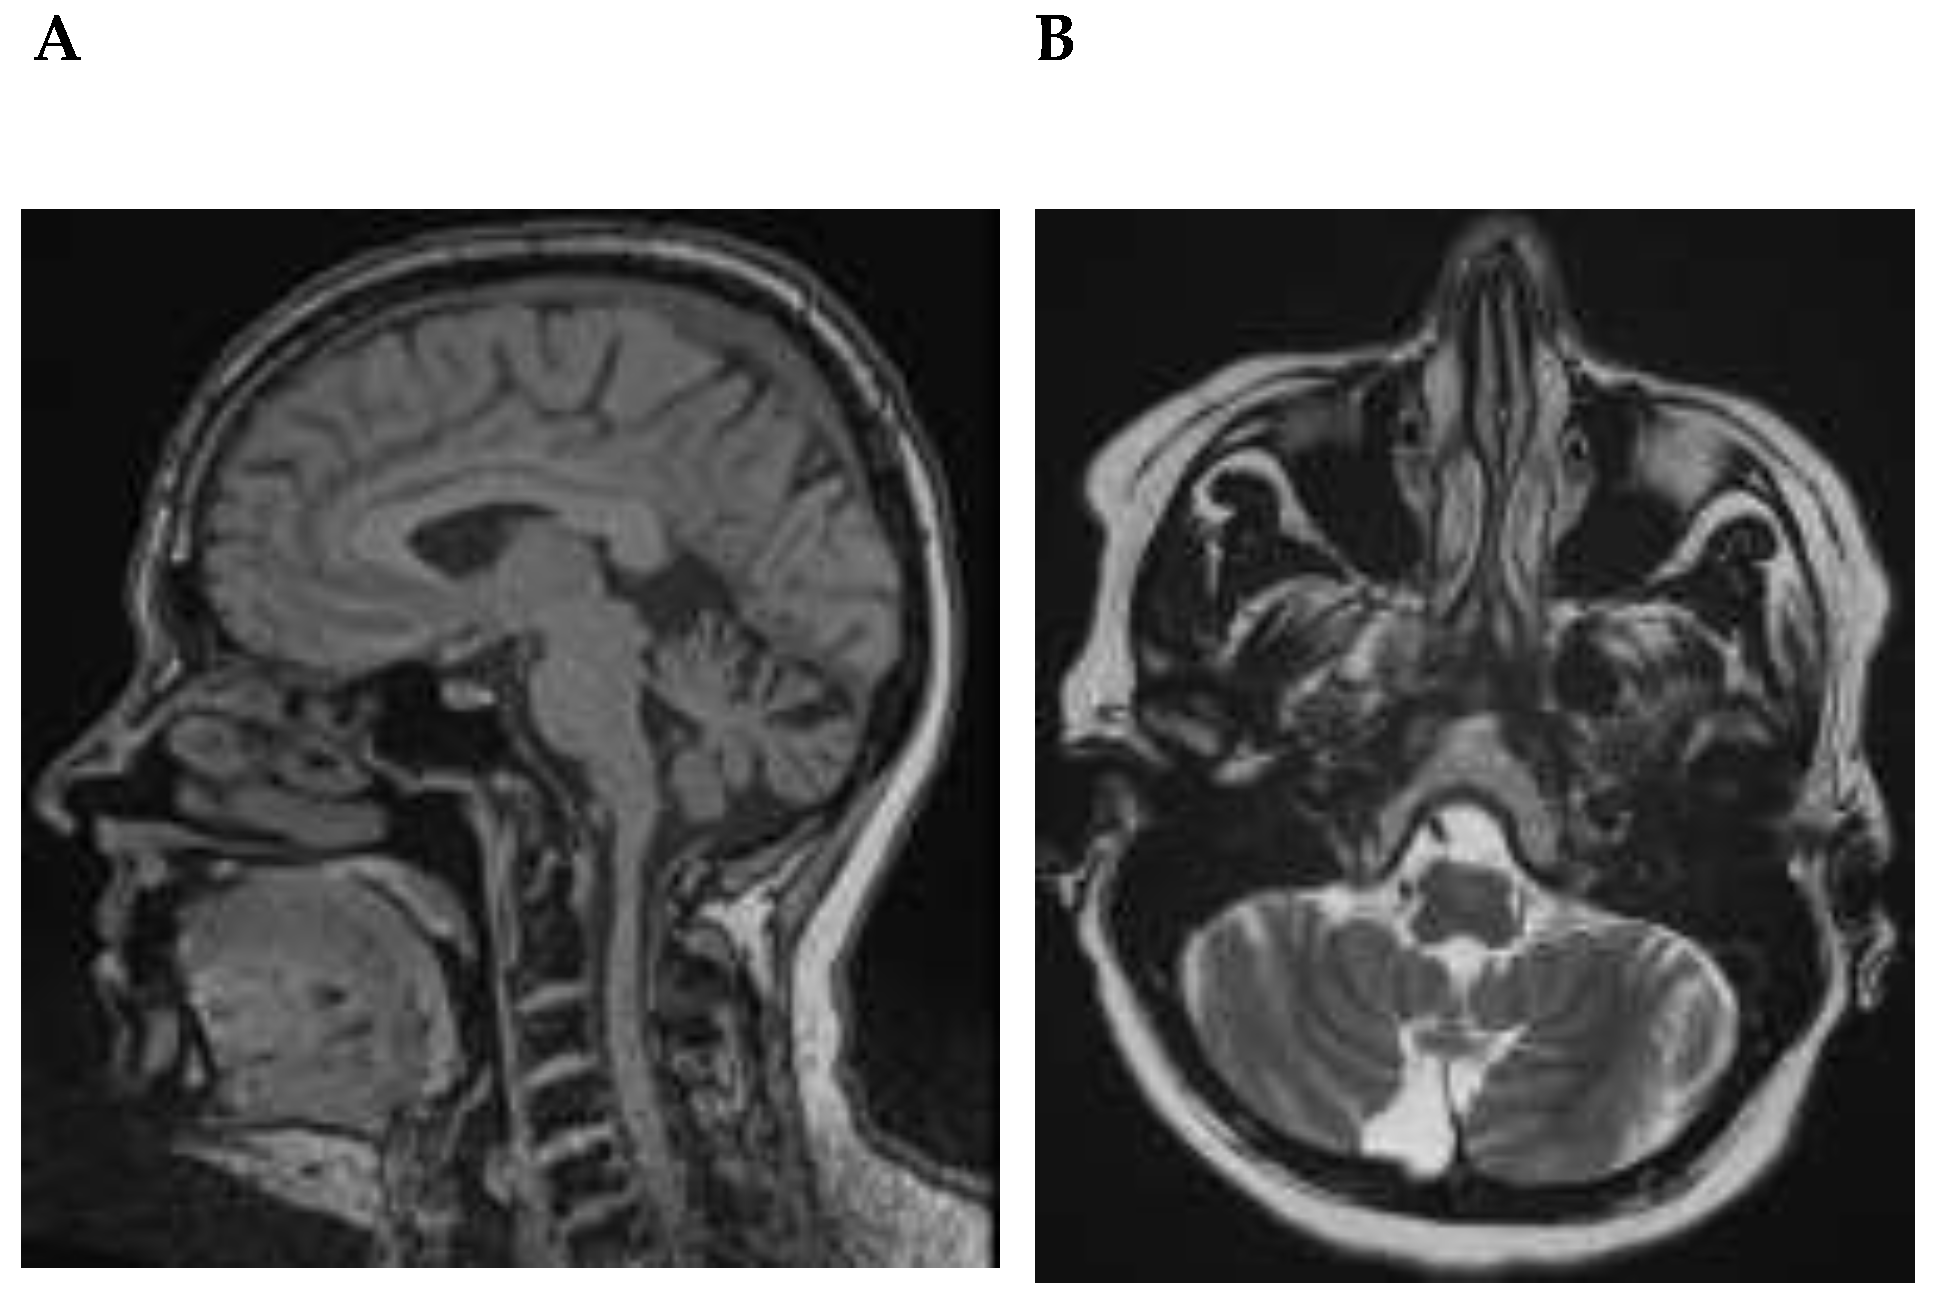

| MRI | |

| Generalized atrophy | 0 * |

| Focal atrophy | 1 # |

| Hippocampal atrophy | 0 |

| Vascular pathology | 0 |